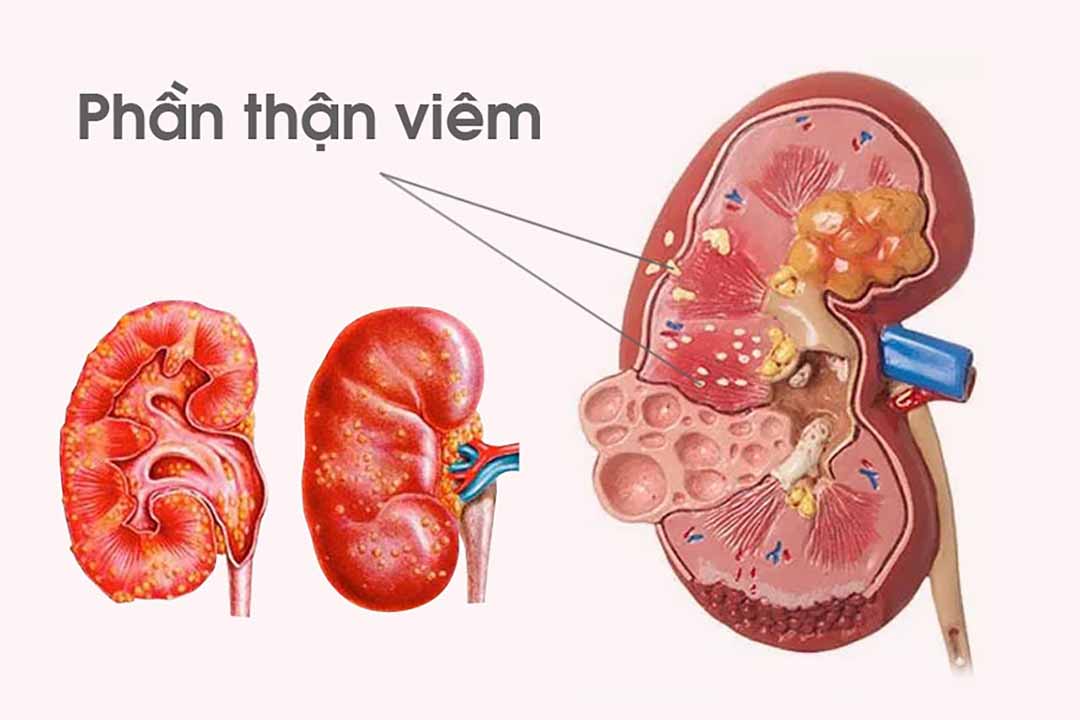

4. Bệnh viêm thận bể thận cấp

Viêm thận bể thận cấp là gì?

Viêm thận bể thận cấp là nhiễm khuẩn tiết niệu trên, gồm nhiễm khuẩn cấp tính các đài thận, bể thận, niểu quản và thu mô thận. Viêm thận bể thận dễ xuất hiện sau nhiễm khuẩn tiết niệu dưới, sau phẫu thuật hệ tiết niệu, tắt nghẽn đường niệu (do sỏi, khối u, xơ sau phúc mạc, có thai, hẹp bể thận niệu quản), có ổ viêm khu trú (viêm bàng quang, viêm trực tràng, viêm ruột thùa, viêm tuyến tiền liệt,…).

Triệu chứng viêm thận bể thận cấp

Các triệu chứng của viêm thận bể thận cấp gồm: Sốt cao đột ngột, rét run, môi khô nứt nẻ, sức khỏe suy sụp nhanh, đau vùng sườn lưng, đau âm ỉ hoặc dữ dội, lan xuống bàng quang và bộ phận sinh dục ngoài.

Bên cạnh đó, bệnh nhân còn bị đau tức hố sườn lưng, tiểu buốt, tiểu rắt, tiểu ra máu, chán ăn, ăn không ngon, chướng bụng, buồn nôn, nôn ói,…